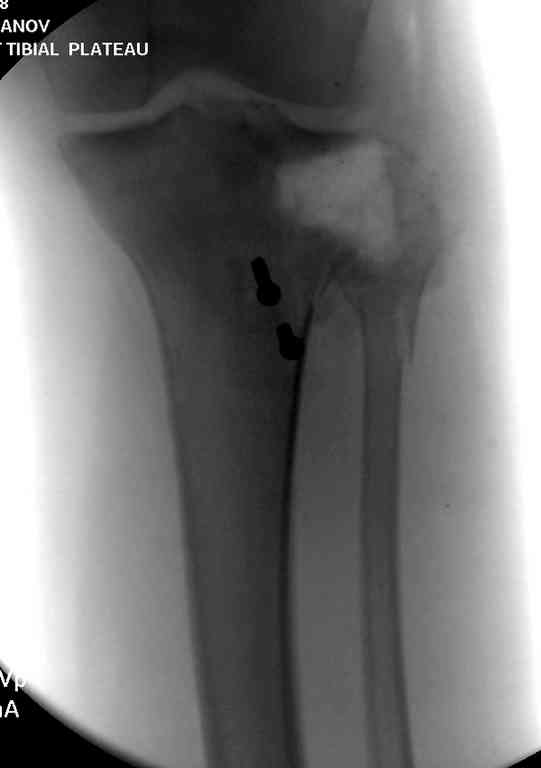

На первом этапе с задачей справляется наружный фиксатор, который создает благоприятные условия для закрытия ран и контролирует длину конечности. На данном этапе рекомендована КТ, чтобы увидеть топографию фрагментов для расчета направления фиксирующих элементов.

Здесь применение материала Plexur http://www.plexur.com для пластики при дефектах кости у больной с огнестрельной раной латерального тибиал плато с повреждением малоберцового нерва. Несмотря на интактный медиальный мышелок, для профилактики от вальгуса установлен АВФ и сделана ангиограмма.

После нескольких обработок и вакуумирования, поэтапно сделана фиксация тибиального бугра шурупами. И окончательную фиксацию закончили латеральной пластиной для тибиал плато и установкой пластического материала.